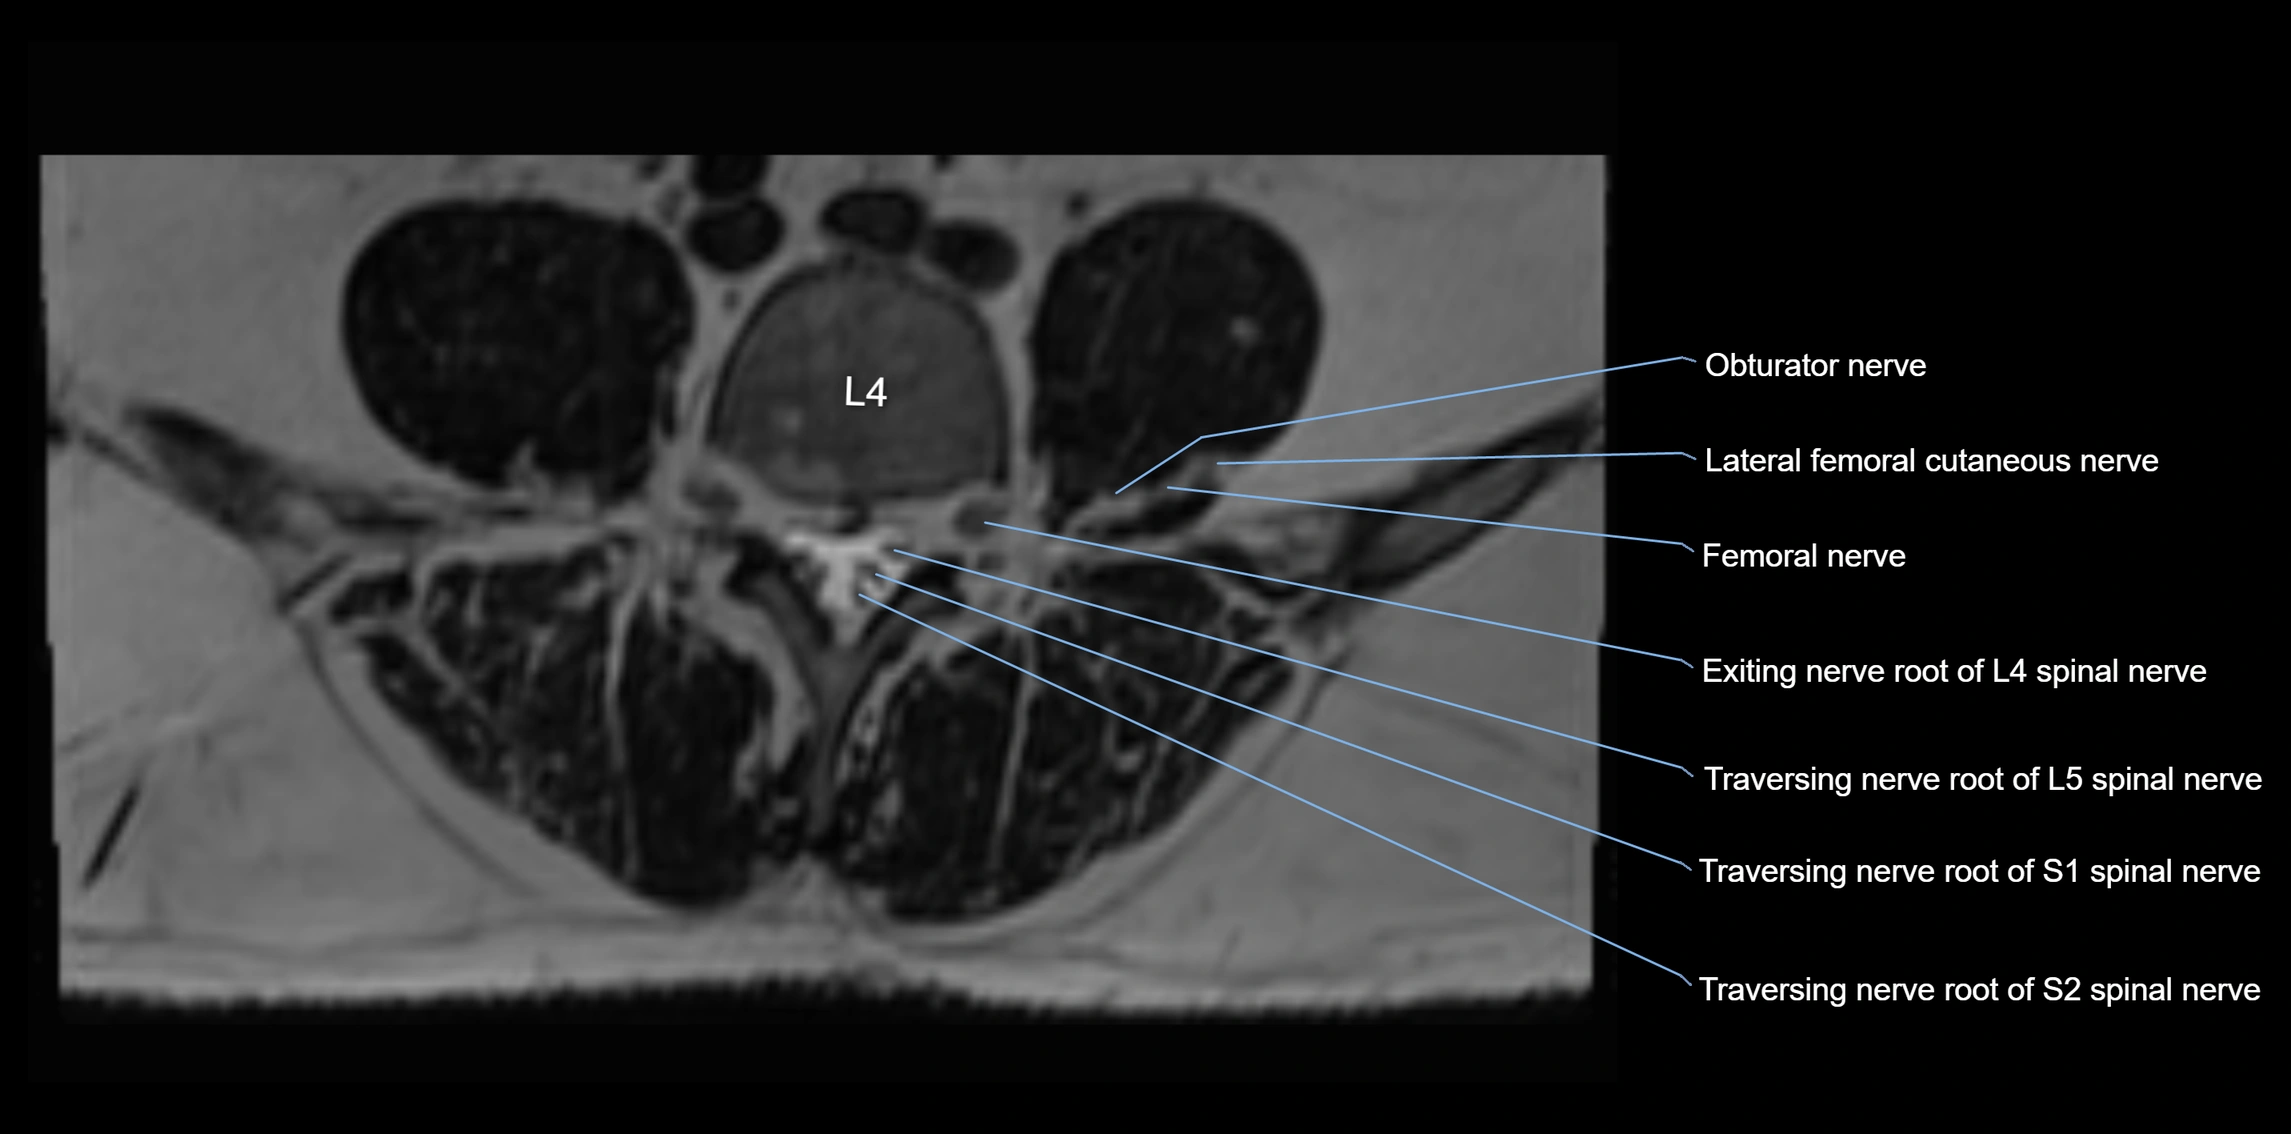

MRI Appearance

T1-weighted images:

• Nerve appears as a very thin low-to-intermediate signal intensity structure

• Surrounded by bright fat, aiding visualization

T2-weighted images:

• Nerve shows intermediate to mildly hyperintense signal compared to muscle

• Pathological involvement appears brighter

STIR (Short Tau Inversion Recovery):

• Normal nerve appears dark

• Inflamed or entrapped nerve appears bright hyperintense

T1 Fat-Sat Post-Contrast:

• Normal nerve enhances minimally

• Pathologic nerve (neuritis, entrapment, tumor infiltration) shows focal or diffuse enhancement

3D T2 SPACE / CISS:

• Nerve appears intermediate to mildly hyperintense compared to muscle

• Surrounded by bright fat or CSF, improving visualization

• Best sequence for mapping small pelvic nerves such as the anococcygeal